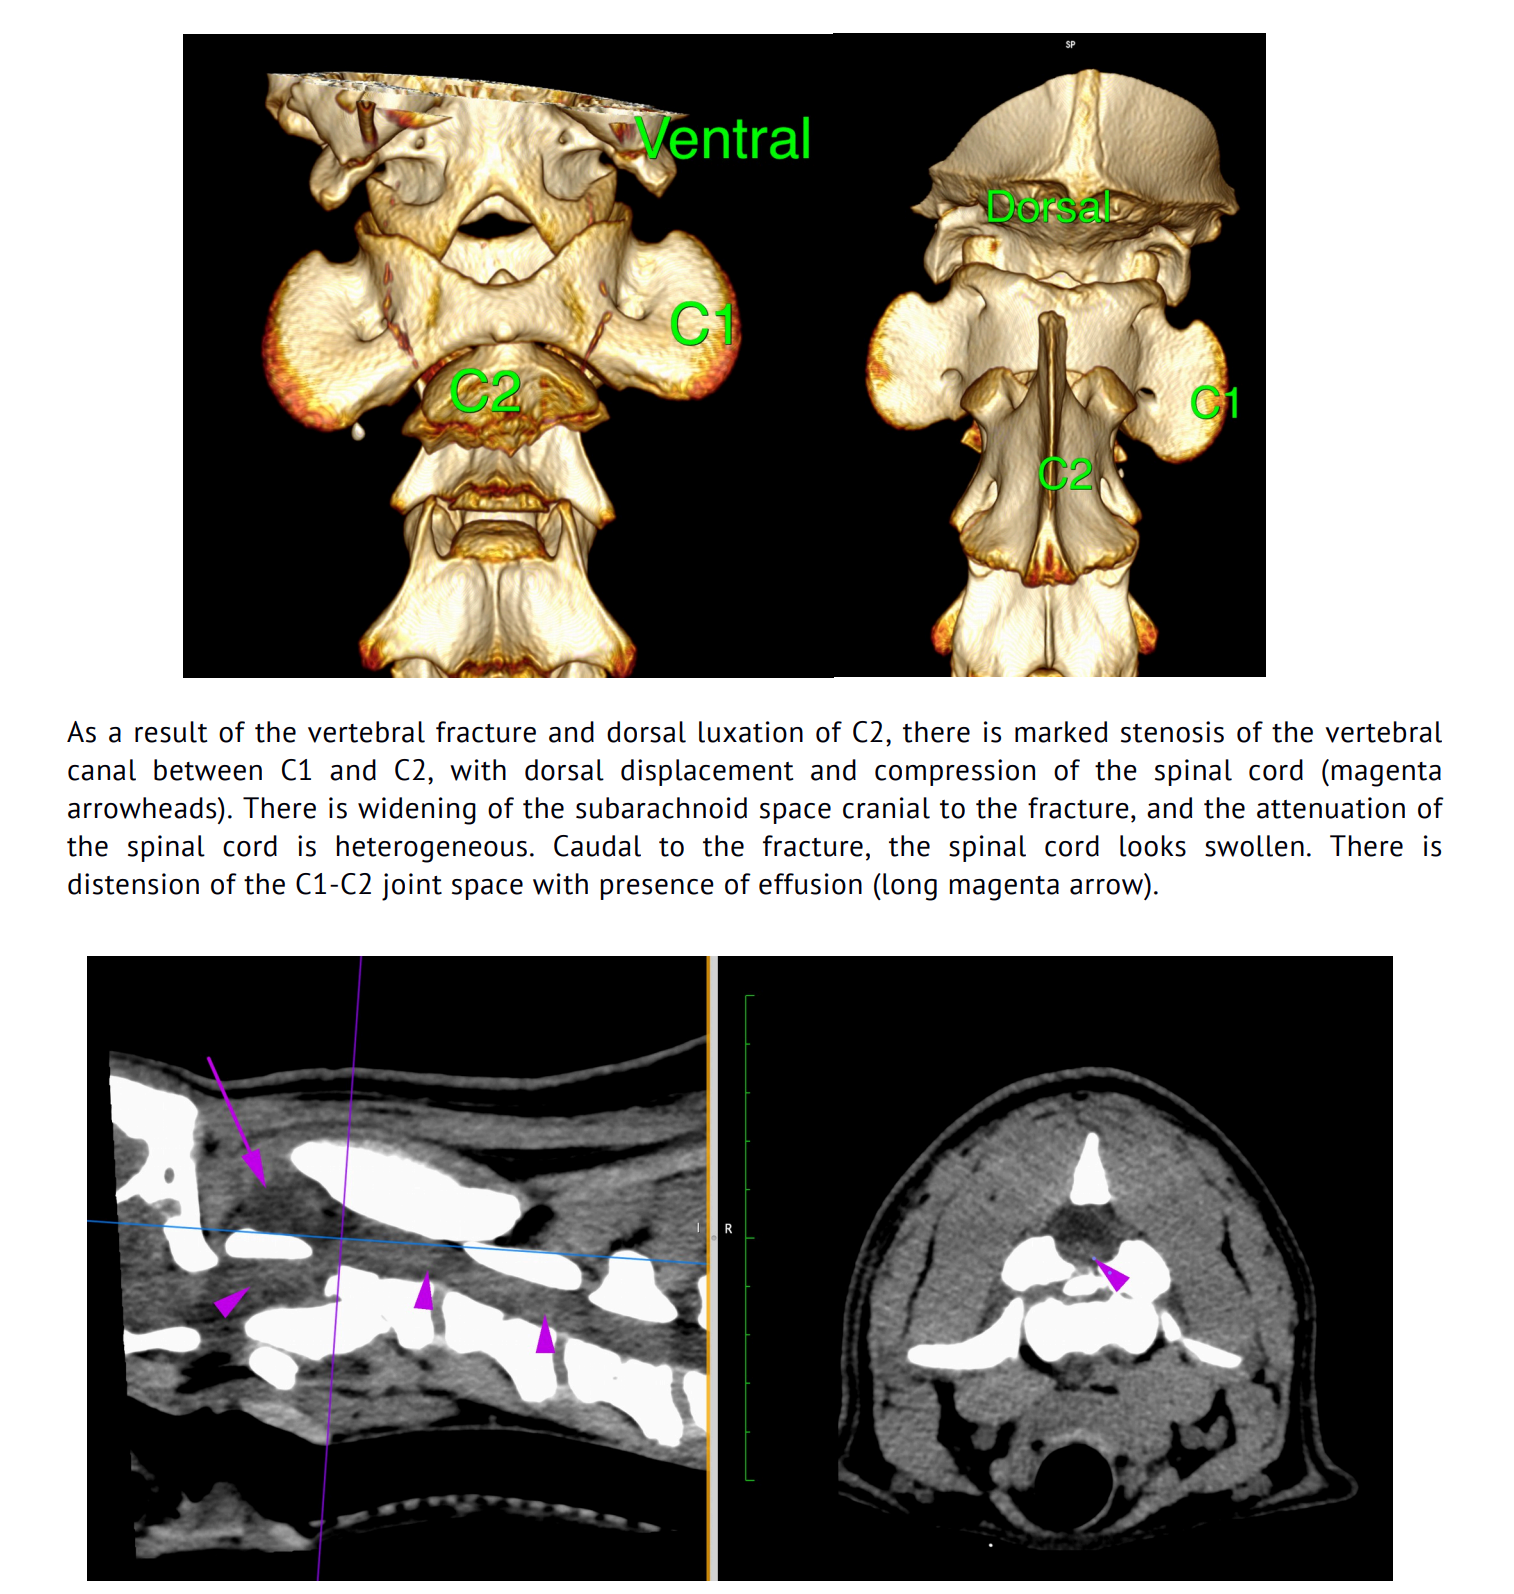

Image: Annotations and reconstructions support clear understanding of diagnostic imaging findings.

Image: Annotated images are an invaluable tool for explaining the rationale behind further diagnostic tests to reach a definitive diagnostic and support compliance with treatment recommendations.